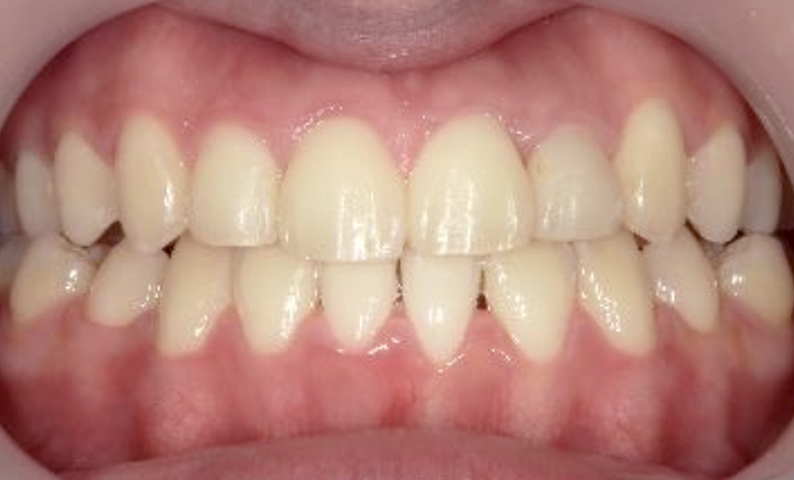

症例_005 上下顎の部分矯正

治療期間:11ヶ月金額:54万円+税女性前歯のガタガタ捻転歯

| Before | After |